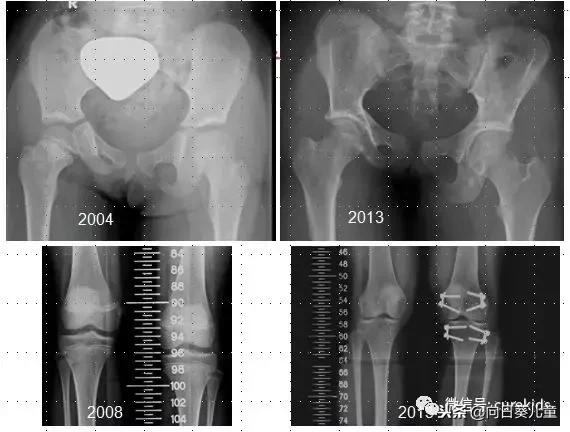

这是我之前治疗的一个患横纹肌肉瘤的小病人,病灶在右侧盆腔,我们看左侧的图片,2004年我们使用的是光子线治疗,而且是比较简单传统型的光子线治疗。

右边图片是九年之后拍的,从这组图片我们可以看出来,后续的影响非常大。我们看这两边骨头看起来好像是等高,但从膝关节这里就可以看到整个右腿发育上受到了很大的影响。

这个孩子后来做了骨头延伸的手术,把两个关节部分拉成一样,保证在行走时的方便,所以放射治疗对正常组织有比较大范围的伤害,但有时我们不会马上看到,要经过很多年,可能5年、10年甚至20年之后,整个伤害的严重性才会慢慢体现出来。